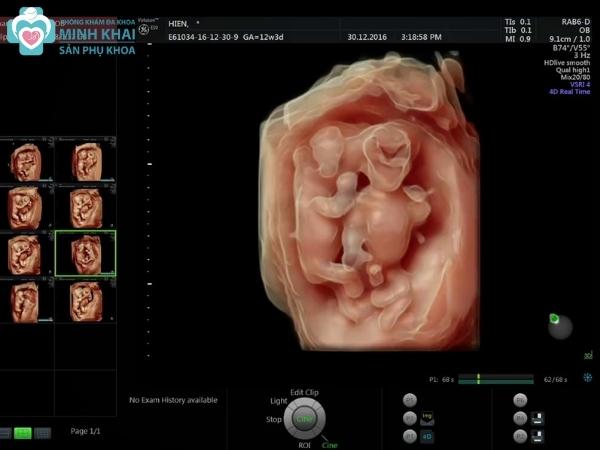

Siêu âm thai 4D

Siêu âm thai 4D phản ánh được hình thái thai nhi bằng các ảnh động nên rất ba mẹ có thể quan sát con rất có thần thái và sống động. Thiết bị 4D có thể bắt trọn được những khoảnh khắc đáng yêu của bé yêu như ngáp ngủ, đưa tay dụi mặt, đạp chân,... Nhờ vậy bạn có thể theo dõi kỹ sự phát triển của con có ổn định hay không và đánh giá rủi ro tiềm ẩn trong thai kỳ để sớm tìm ra hướng giải quyết tốt nhất.

Ngoài ra, kỹ thuật siêu âm 4D cũng được đánh giá là an toàn và không gây ảnh hưởng đến sức khỏe thai kỳ. Nó còn cung cấp hình ảnh, thông số siêu âm giúp chẩn đoán chính xác được nhiều dị tật phổ biến ở trẻ lên đến 90%.

Siêu âm 4D thể hiện được cấu trúc bên ngoài và nội soi cấu tạo bên trong của thai nhi qua hình ảnh không gian 3 chiều trong cùng một chiều thời gian. Vậy nên nó có thể tái hiện lại hoạt động của thai nhi qua ảnh động hoặc video ngắn